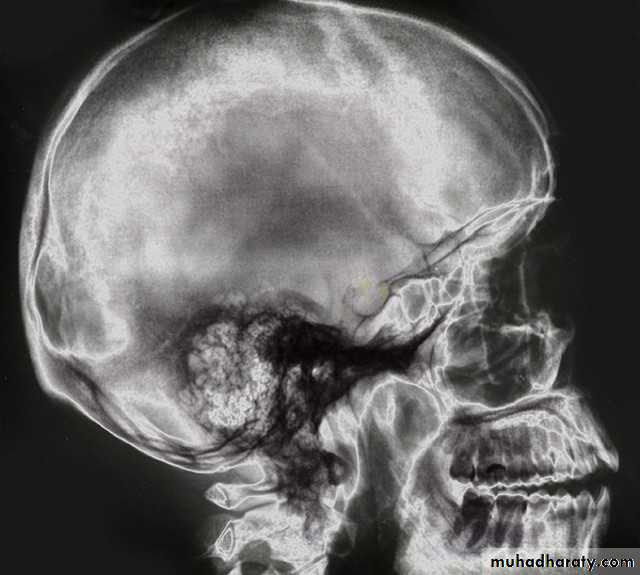

• A-Plain film: which have limited role in the radiological evaluation of facial trauma. Include:

• -Skull film(lateral and posteroanterior view).

Skull film

Lateral viewP-A view